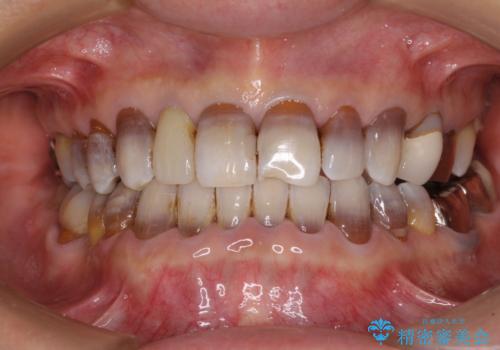

下の歯が前に出てしまう咬み合わせを治したい インビザラインによる矯正治療

- 前歯のクロスバイトを気にして来院された患者様です。

骨格的に下顎が前方位ではありますが、歯並びが改善されれば正常咬合となることが分かったため、インビザラインを用いて咬み合わせを改善していくこととしました。

インビザラインは四六時中上下のマウスピースを介した咬合状態となるため、治療過程にて奥歯が接触しないという状態が続くことがあります。

奥歯の非接触は機能面において大きな障害であるため、この問題を解決しない限り矯正治療を終えることはできません。

インビザラインでの矯正治療が長期化してしまう要因の1つです。